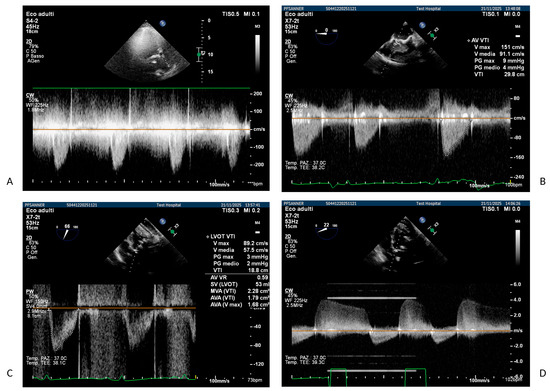

The Middle Meningeal Artery (MMA) occupies a pivotal role in the pathophysiology of migraine, functioning as a vascular and neuroimmune interface that precipitates the characteristic pulsatile pain. The inhibition of this pathophysiological cascade has been investigated as a therapeutic strategy. However, fewer than a dozen centers globally have disseminated procedural or mechanistic data. Given the nascency of this field and the imperative for standardization, the present review synthesizes mechanistic and clinical evidence underpinning intra-arterial pharmacological modulation of the MMA for migraine management. Methods: A focused narrative review was undertaken, drawing upon select but influential studies from pioneering research groups investigating intra-arterial interventions targeting the MMA. The extant literature was thematically categorized and organized according to the loci of cascade interruption and their corresponding clinical outcomes. Results: Since 2009, intra-arterial therapies for severe headache syndromes have evolved, initially utilizing nimodipine for vasospasm-related headaches, progressing to verapamil for reversible cerebral vasoconstriction, and more recently, lidocaine for refractory or status migrainosus, occasionally in conjunction with MMA embolization. Contemporary research uses language that conceptualizes migraine as an immunologically mediated neurovascular disorder, as opposed to a purely vascular or neuronal entity. Recent investigations have identified interleukins such as Interleukin-1β, Tumor Necrosis Factor-α, and Interleukin-6 as critical amplifiers of trigeminovascular activation. Purinergic signaling through the P2X3 receptor and the P2Y13 receptor, in conjunction with pituitary adenylate cyclase-activating polypeptide and vasoactive intestinal peptide pathways, has been implicated in the modulation of MMA excitability and neuropeptide release. The development of novel calcitonin gene-related peptide receptor antagonists, such as zavegepant, further substantiates the artery’s significance as a pharmacological target. Conclusions: These findings support a shift toward immune-modulating intra-arterial therapeutic strategies, with migraine interventions targeting cytokine and neuroimmune signaling within the MMA, rather than relying exclusively on vasodilatory mechanisms.